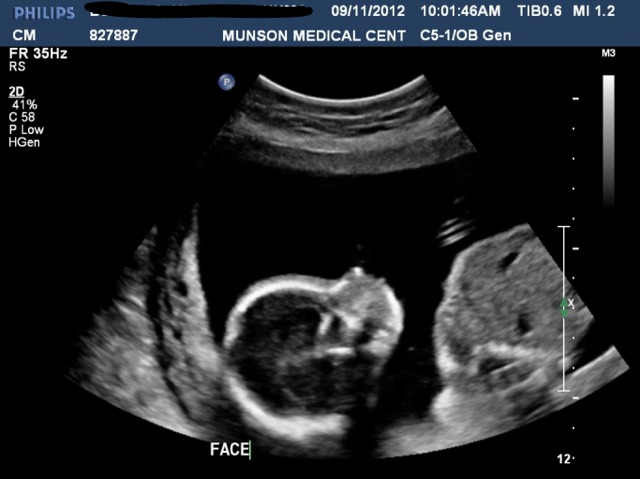

Sweet lil profile...

Attachment 4516